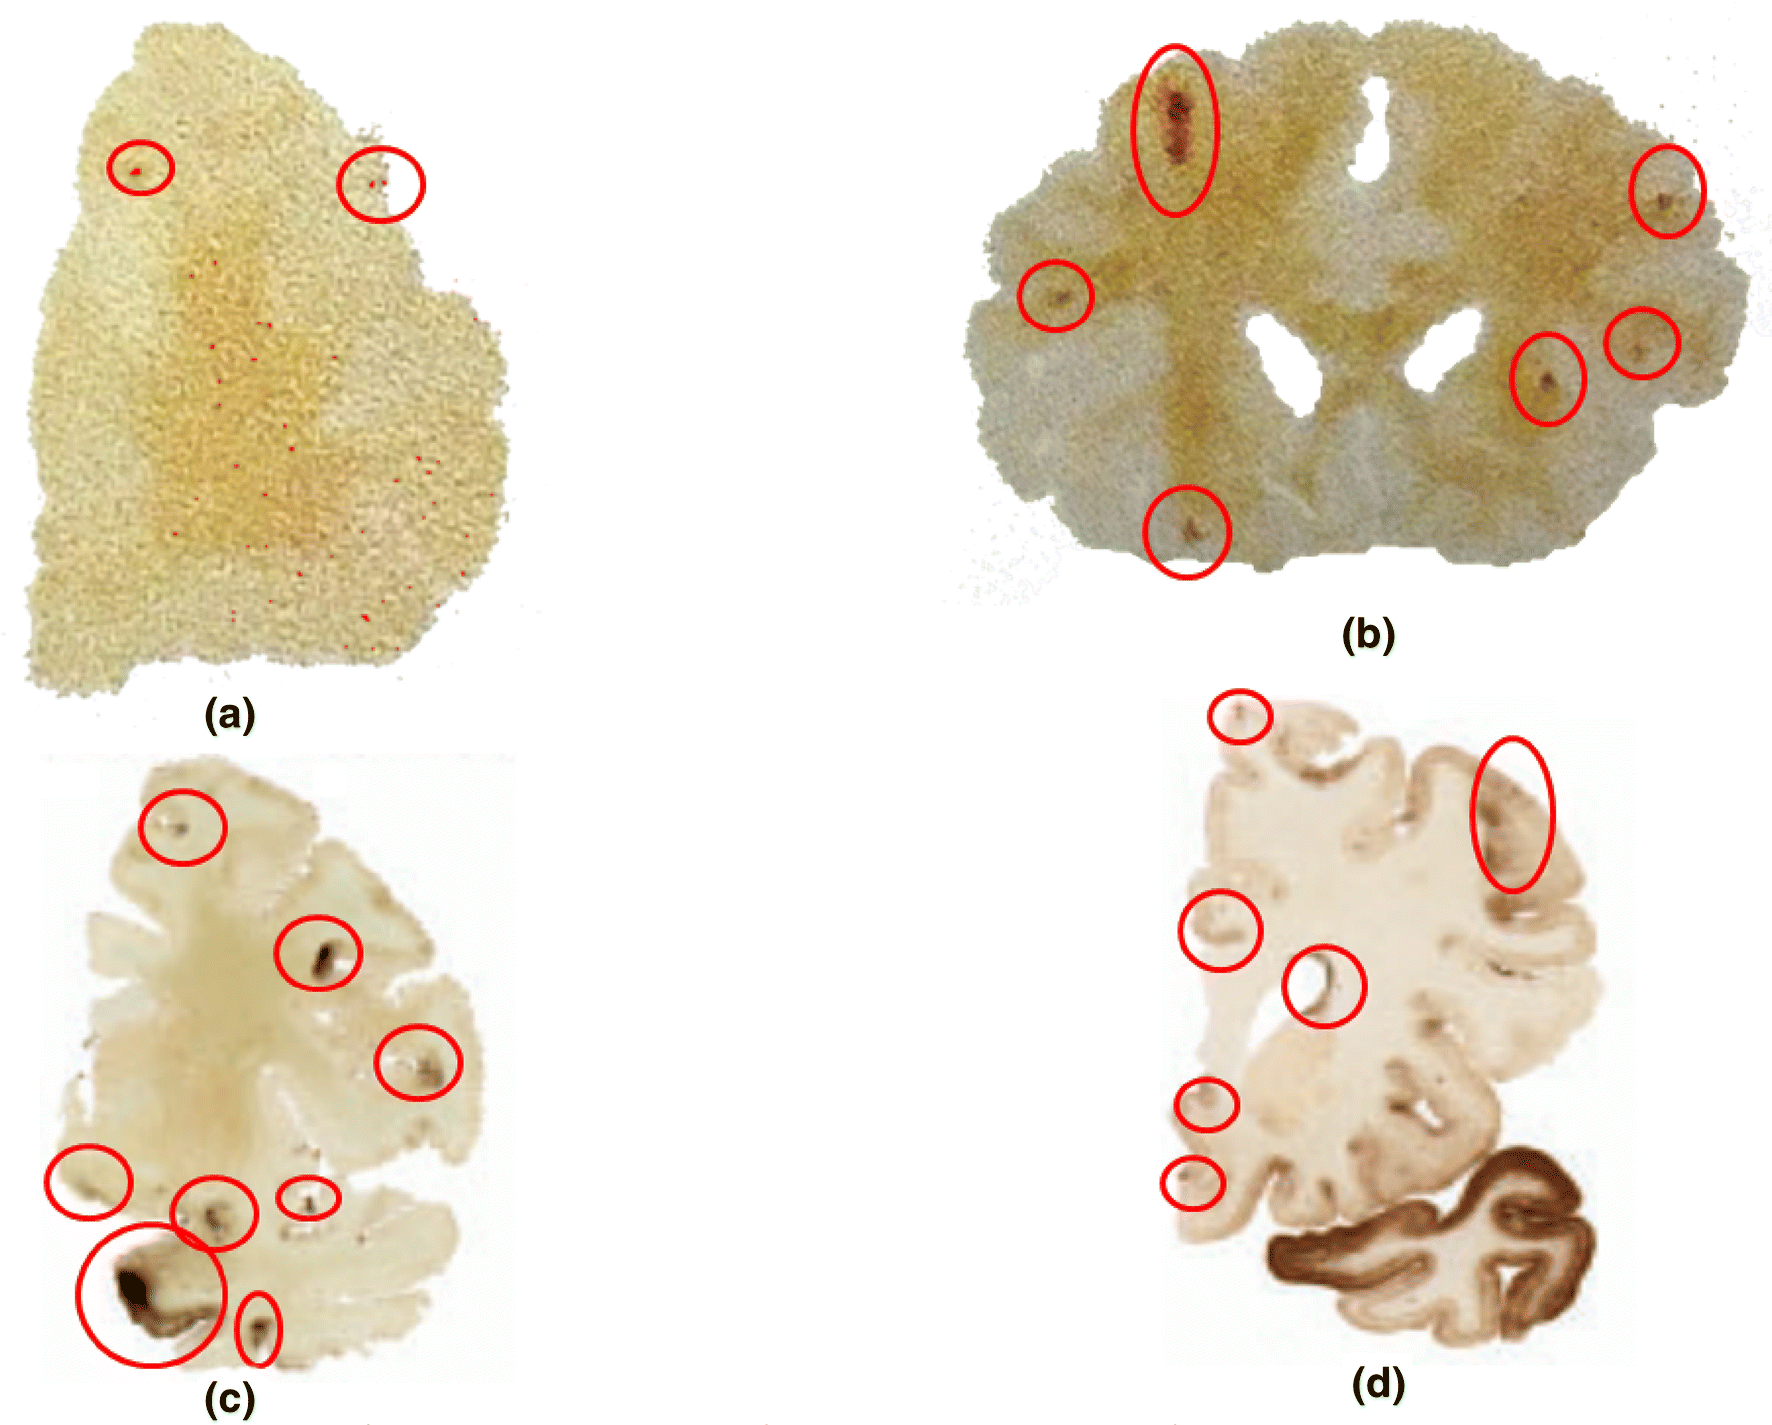

A Mechanical Brain Damage Framework Used to Model Abnormal Brain Tau

Immunoreactive ET1 protein expression by confocal microscopy of HUVEC

Neurochemistry CH 12 Accumulation of Abnormally Processed Tau

ET1 secretion by EOC cells requires βarr1 and HIF1α. A. ET1 protein